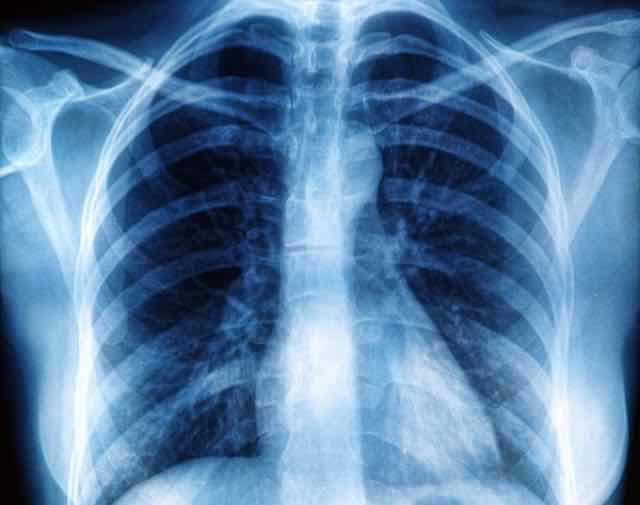

A divulgação errônea de que por meio de tomografias é possível verificar se a Covid-19 está presente em determinado paciente, ou até mesmo o estágio da doença, faz com que pessoas procurem médicos radiologistas para fazer tomografias computadorizadas, ressonâncias ou mesmo radiografias em busca de diagnósticos.

“A tomografia computadorizada ou a radiografia de um paciente com Covid-19 podem não mostrar a presença da doença, principalmente nos primeiros dias.  As pessoas acham que estes exames podem diagnosticar o novo coronavírus, mas não é bem assim”, afirma Camilo Dallagnol, médico especializado em Radiologia e Diagnóstico por Imagem do Plunes Centro Médico e com atuação na Precisão Diagnóstico por Imagem, ambos em Curitiba.

Ele explica que um paciente pode ter desde um quadro assintomático, passando por um resfriado e até uma pneumonia, que seria a forma mais grave da doença, e seria justamente neste último caso que os exames de radiografia e tomografia teriam seu papel.

“As alterações nos pulmões causadas pela Covid-19 costumam aparecer nas tomografias de pacientes com pneumonia após alguns dias do início dos sintomas, geralmente com um tipo de alteração que nós chamamos de vidro fosco. Depois podem aparecer outros tipos de alterações, como linhas e consolidações. Já as radiografias são menos sensíveis, ou seja, detectam menos a doença, principalmente nesses estágios iniciais, quando há presença de apenas vidro fosco”, detalha. Segundo o especialista, os exames de imagem podem dar indícios e apontar com grande suspeição o diagnóstico da Covid-19, mas não substitui os métodos laboratoriais, como sorologias e proteína c-reativa (PCR) para o diagnóstico definitivo

Dallagnol também informa que o exame pode mostrar informações que não são fáceis de distinguir daquelas provocadas por outras doenças, como outros tipos de pneumonia.

“Mesmo quando evidenciamos alterações nos exames de imagem, eles podem ser inespecíficos. Pode ser impossível diferenciar de uma outra doença, como uma pneumonia por influenza (gripe). Já cheguei a ver na mídia e em redes sociais pessoas utilizando o termo ‘vidro fosco’ como um sinônimo da Covid-19, sendo que uma grande quantidade de doenças pulmonares podem apresentar este tipo de alteração”, explica.

Segundo o especialista, a tomografia não pode ser utilizada indiscriminadamente e não substitui os métodos de sorologia e proteína c-reativa (PCR) no diagnóstico da infecção pelo novo coronavírus. “O que a tomografia traz são informações complementares sobre a pneumonia causada pela doença e que ajudam a presumir o diagnóstico enquanto ele não é confirmado pela PCR e ajudando a estimar a gravidade do caso”, finaliza.